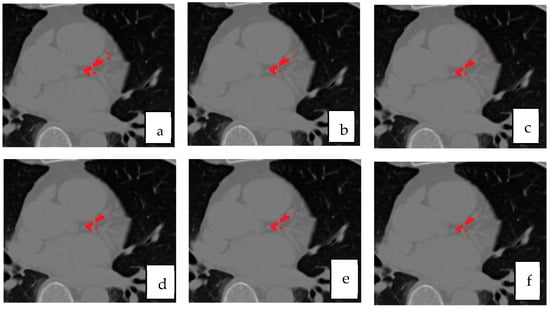

To quantify the contribution of each component within the proposed framework, an ablation study was conducted as summarized in Table 4. Using only the best single model (Residual U-Net) serves as the baseline configuration, representing the strongest standalone learner in our architecture set. Introducing a simple soft-voting ensemble of all U-Net variants yields modest gains, reflecting the benefit of aggregating heterogeneous feature representations but still limited by uniform weighting.

Replacing soft-voting with the proposed rank-based selective fusion provides a more pronounced improvement, as the ranking mechanism prioritizes morphologically consistent, vessel-aligned predictions while suppressing isolated or anatomically implausible responses. The addition of vessel priors to this selective ensemble further refines localization by spatially constraining calcifications to the coronary tree, leading to the highest Dice and sensitivity scores overall.

As observed, the rank-based ensemble improves Dice by approximately +0.95% over soft-voting, while incorporating vessel priors adds a further +1.25% Dice and +1.4% sensitivity gain. These progressive improvements demonstrate that anatomical guidance complements ensemble diversity, yielding the most anatomically coherent and clinically reliable CAC segmentation results.

Figure 8 presents qualitative examples illustrating the progressive improvement across different configurations. The final model with vessel priors produces cleaner, vessel-aligned lesion maps and sharper calcification boundaries compared to the baseline and soft-voting ensembles. The addition of selective fusion and vessel priors progressively improves lesion sharpness, vessel conformity, and reduces false positives around extracardiac regions.

Figure 6. Qualitative comparison of segmentation results for coronary artery calcification (CAC). (a) ground truth mask, (b) proposed selective ensemble, (c) Residual U-Net, (d) UNet++, (e) Attention U-Net, and (f) baseline U-Net.